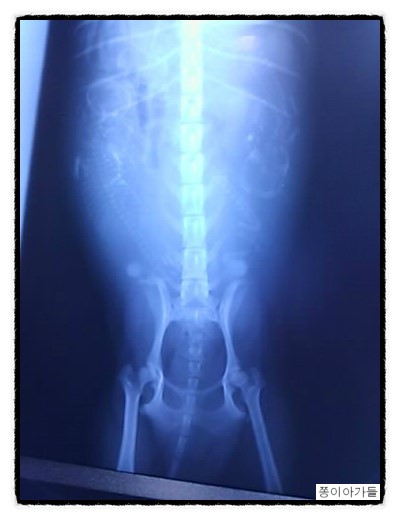

새끼들이 잘 자라고 있는지 X-ray를 통해 확인하기도 했다.

쫑이 아가들의 X-ray 사진